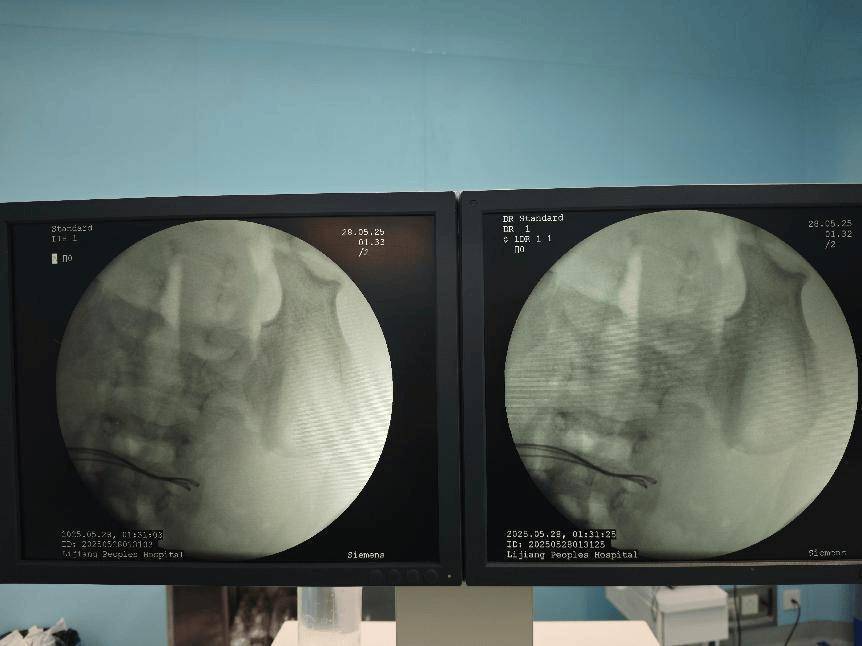

术中取出小肠异物

经过研判,医疗团队凭借着精湛的技术和坚定的信念,克服了重重困难,成功取出了该病人体内的37颗磁力珠,并对穿孔部位进行了细致的修补拜仁慕尼黑足球 。经过数小时的紧张手术,通过腹腔镜、内的联合操作,让病人脱离了生命危险。

术中完善床旁DR见腹腔内已无异物